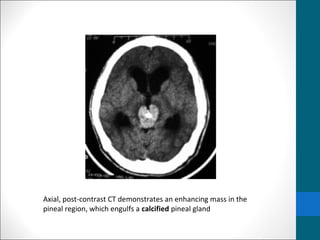

• Computed tomography (CT) scanning may be needed to

evaluate a calcified pineal gland that is associated with a

pineal germinoma or tumor calcification associated with

other neoplasms in the pineal region.

• Germinomas are associated with a high incidence of

pineal gland calcification.

• The tumor does not calcify, but it may engulf a calcified

pineal gland.

• Nonenhanced CT scans

• Typically demonstrate a slightly hyperattenuating

mass that engulfs a prominent calcified pineal gland.

• Contrast-enhanced CT scanning

• demonstrates homogeneous and intense

enhancement.

Axial, post-contrast CT demonstrates an enhancing mass in the

pineal region, which engulfs a calcified pineal gland

Axial, post-contrast CTdemonstrates an enhancing mass in the pineal region, which engulfs a calcified pineal gland